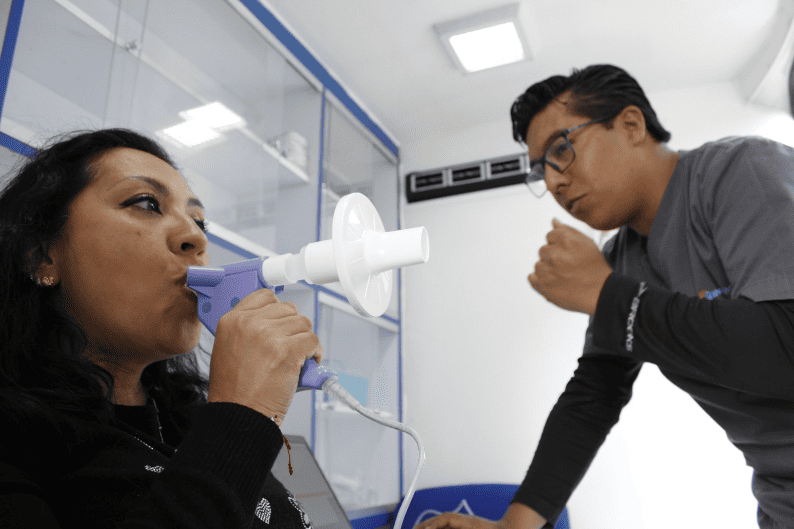

La espirometría es una prueba sencilla y no invasiva que mide la capacidad y el flujo de aire en los pulmones, ayudando a diagnosticar y monitorear enfermedades respiratorias como asma, EPOC y fibrosis pulmonar. Sus beneficios incluyen la detección temprana de afecciones pulmonares, la evaluación de la respuesta al tratamiento y el control preciso de la función respiratoria, mejorando la calidad de vida del paciente.

Se realizan estudios como espirometría, oximetría de pulso o radiografía de tórax, según cada caso, para obtener un diagnóstico preciso y diseñar el mejor plan de tratamiento.